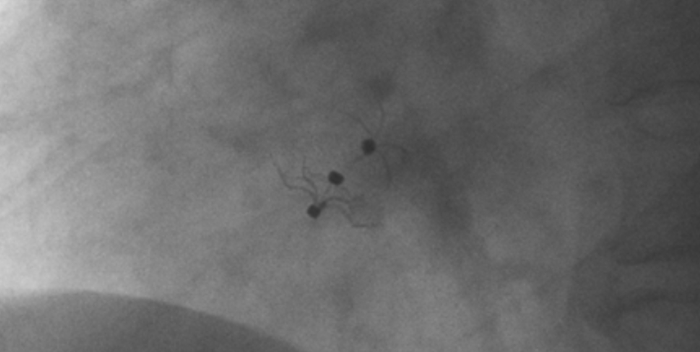

术中造影显示患者为PFO且长隧道型,目前市场上已商业化的PFO封堵器难以满足该患者解剖结构封堵需求。迪创医疗自主研发的OmniSeal PFO封堵器自适应性双盘贴合设计能广泛适应不同PFO隧道长度的解剖结构和形态,其双盘外包覆式阻流和隧道内填充阻流相结合的双重阻流设计,可为此患者实现有效封堵。与此同时,OmniSeal首创的完全可穿刺式设计,也为此患者最大程度地保留了房间隔区域穿刺通道,以实现全兼容未来可能的左心系统二次介入术。术终造影和心脏超声显示封堵完全、效果良好。作为OmniSeal的首例临床应用,本次手术的顺利完成和优异效果充分体现了产品的设计创新优势。

造影显示PFO封堵完全,无残余分流,

试验器械充分舒展并贴合良好